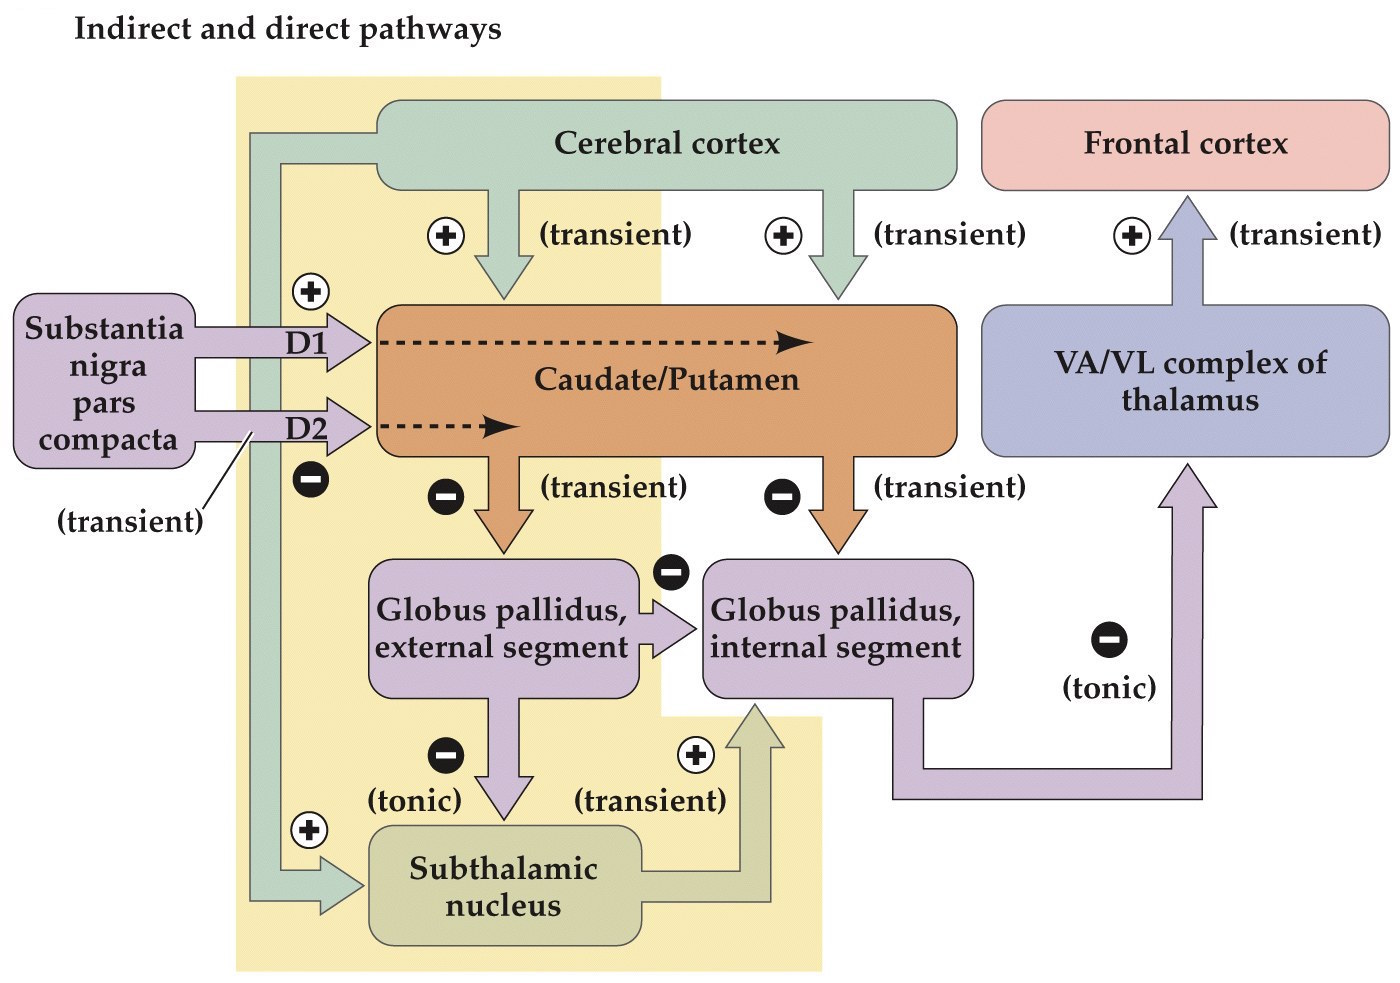

Indirect pathway circuits

- Provides a second route of influence via a loop back to the direct pathway

- MSN neurons also project to the globus pallidus external (GPe) nuclei which then project to the subthalamic nucleus (STN) of the ventral thalamus

- STN neurons project back to GPi which then projects out of basal ganglia to the VA/VL complex of the thalamus

- Subthalamic projections are excitatory which increases the inhibition of GPi. Opposite/antagonistic of the direct pathway. Acts as a brake to prevent too much disinhibition of upper motor neurons

- Decreases upper motor neuron activity

Dopaminergic neurons modulate direct and indirect pathways

- Medium spiny neurons (MSNs) in striatum project to the substantia nigra pars compacta (SNc), which in turn projects back to MSNs

- Both MSNs that project to GPe and GPi receive these inputs

- Those that project to GPi have type D1 receptors (coupled to a Gαs, excitatory) and those that project to GPe use type D2 receptors (Gαi, inhibitory)

- Dopamine excites the direct and inhibits the indirect pathway

Direct and indirect pathways through the basal ganglia

Dopamine excites the direct and inhibits the indirect pathway.

Hypokinetic and hyperkinetic disorders summary

- Parkinson's– hypokinetic disorder. More tonic inhibition of thalamus and decreased excitation of frontal cortex

- Huntington's– hyperkinetic disorder. Less tonic inhibition of thalamus and more excitation of frontal cortex